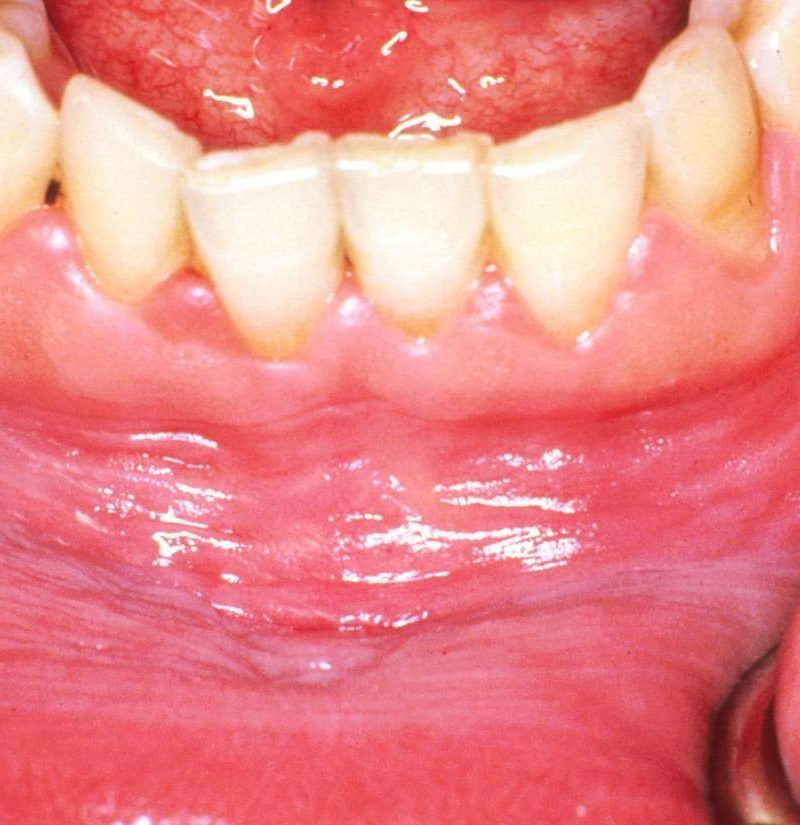

Healthy gums are coral pink, firm, and fit snugly around the base of each tooth. They do not bleed randomly, they do not swell without cause, and they definitely do not turn white.

Any change from that baseline whether it is white color on gums, unusual paleness, or even gums color black patches in certain areas is your mouth sending a signal worth paying attention to. The question is always what that signal means and how quickly you need to respond.